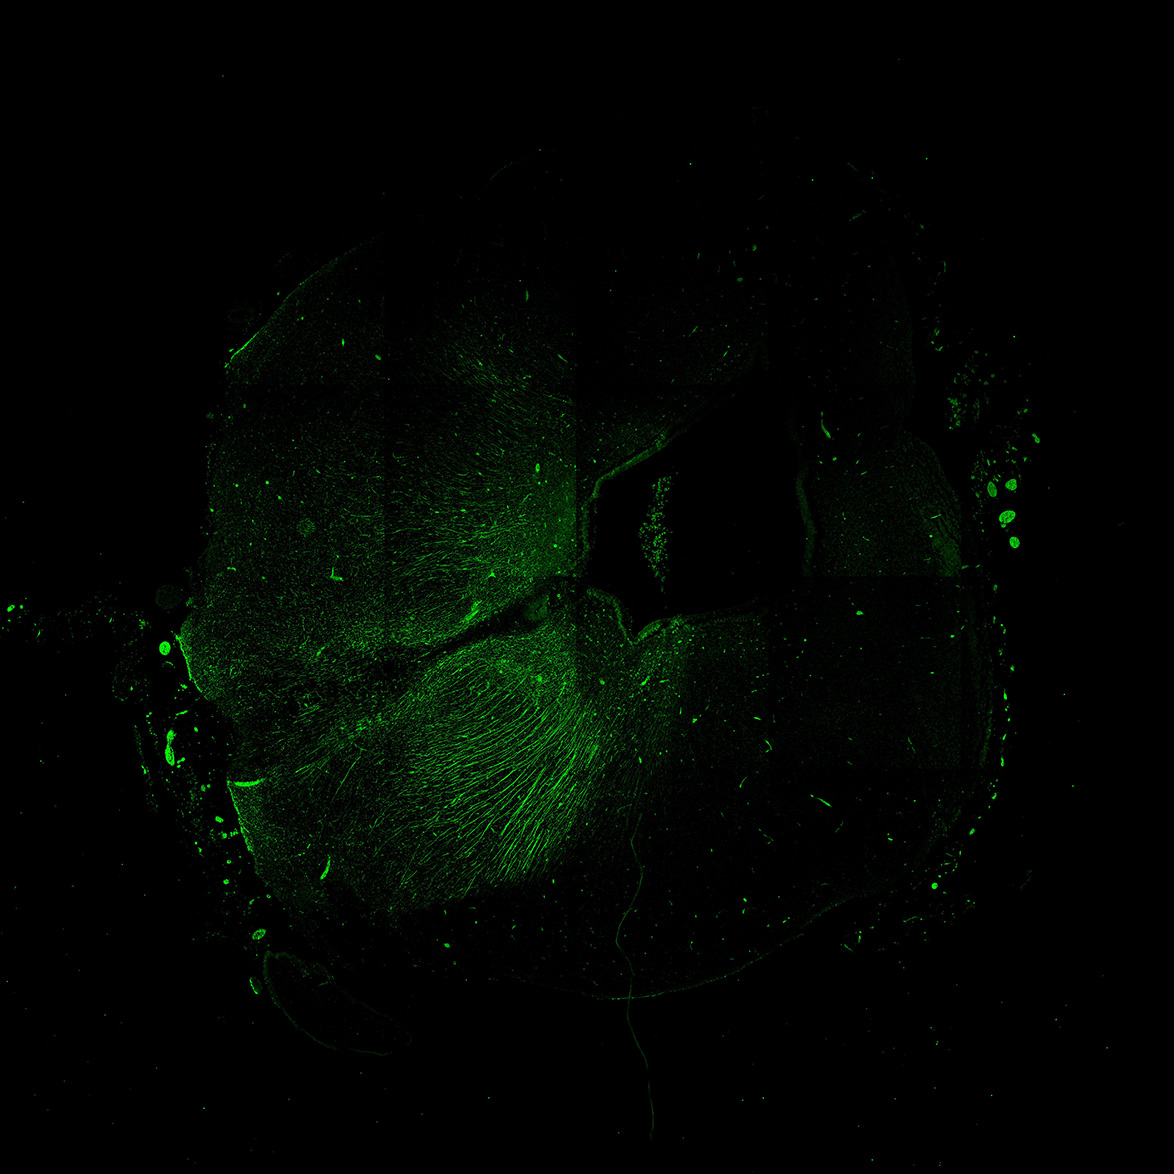

An anatomical analysis of the developing human midbrain from 6 post-conceptional weeks (PCW) to 22 PCW reveals increased tissue complexity, characterized by the emergence of dopaminergic nuclei, as highlighted by immunofluorescence analysis for tyrosine hydroxylase (TH).

19PCW

DAPI

19PCW human midbrain

MAP2

TH

Merged